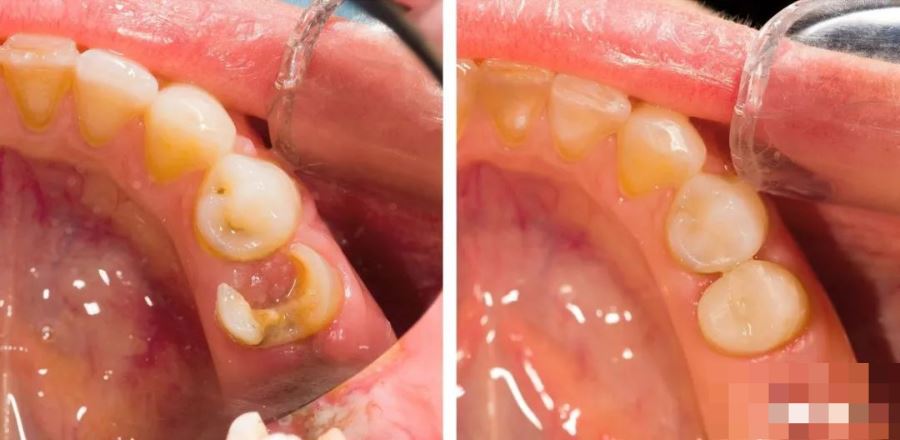

大致步骤为:去净?;担票付葱?。隔湿,消毒,干燥,垫底,酸蚀,冲洗、干燥,涂粘结兰梦婷剂,光照,光固皇家贵族指环有什么用化复合树脂分层充填,抛光。1、去净龋坏时,小心不要穿髓。龋洞比较深时,用挖勺挖去洞底龋坏组织相对安全些。洞型边缘用金钢砂打磨金安高宝影城成45℃斜面。目的:增加粘结力。再去除弱尖薄壁釉质,从而防止洞缘白线的产生。2、排龈。工作牙的邻间隙放一小棉球,可吸收龈沟液。3、过深的窝洞近髓处要用光固化氢氧化钙衬底,衬底前要用棉球隔湿,酒精消毒,三用枪干燥,衬底厚度不超过2mm,并光照10秒。注意:无粘接性垫底材料不应过多覆盖牙本质,更绝对不得覆盖釉质。4、酸蚀剂酸蚀30~60秒,用小棉球擦拭掉半结固状(膏状)酸蚀剂后,用三用枪彻底冲洗酸蚀后的创面15秒,干燥创面(干燥程度根据粘接剂说明书要求):轻吹三下或者棉球擦干。注意:酸量勿多,处理部位应准确不得酸蚀活髓牙本质。5、用直径2~3mm的小棉球(具体根据洞的大小制作棉球)蘸光固化粘接剂涂抹备好的窝洞内壁,涂抹粘结剂的时候,要动态涂抹,就是说要用小棉球不断涂抹5秒(涂抹时间根据说明书要求)。轻吹粘接剂,使之均匀涂满窝洞内表面,光照10秒。6、光固化树脂充填过深的窝洞时,应分层充填,使用三明治技术,每层最厚不得超过2mm,否则光固化灯不易照透,光固化至少20秒,隔牙照射,以防树脂光照结固收缩产生缝隙。7、相邻两牙都有窝洞时,先充填好一个牙,光照、抛光后,用树脂成型片包裹住充填好的牙,然后再充填另一个牙。树脂成型片在涂抹粘结剂后再置入。8、使用专门的充填器械,会有效的避免树脂沾器械,不可以于充填器上涂抹酒精或粘结剂来塑形树脂,因为可造成固化不全(酒精可融解树脂单体;粘结剂全是基质无填料造成树脂性能下降)1、把握住细节,读懂说明书,尽量不要按照个人习惯使用树脂材料。2、了解要使用的材料信息(什么牌、第几代等),材料需要哪些要求(比如湿粘结、涂布、吹干等)。3、隔离唾液和龈沟液(据文献表明。龈沟液的每分钟的分泌量很大,每小时可替换40次左右)4、树脂的厚度(一般来说管固化在保证固化强度后最多只能穿透2MM的数字,所以充填树脂必须分层固化)分层张泊远填充的时候宁薄勿厚,树脂需要人字形填充,最好加热增加流动性,不然边缘难以严密。5、光照时间(必须严格按照树脂说明书标注的时间,不能自己随意缩短)建议每周检测下光固化灯的强度,如果强度不够。需要调整或者增加光照时间。6、修型和抛光。许多人抛光不好造成种植问题。抛光后后牙可以涂布一种特殊的粘结剂,封闭会更好,避免光照后收缩引起的微小细纹,避免微渗漏,并且更硬,避免氧化层,减缓树脂老化。1、上前牙邻面外展隙远中要比近中大些,中切牙邻面接触点恢复在近切端50%处;侧切牙40%;尖牙30%处。2、流动树脂可缓解光固化收缩的问题,适合用在本质支持少的部位来减少固化收缩产生的釉质破裂问题。3、涂抹粘结剂的时候,要动态涂抹,就是说要用海绵小刷子不断涂抹15~20秒再光照。4、不足1mm近髓处,采用氢氧化钙垫底,否则可用流动树脂垫底。5、注意c-factor,采用三角充填法,避免固化牵张效应。6、洞型边缘用小球钻打磨,再抛光去除弱尖薄壁釉质,从而防止洞缘白线的产生。7、树脂黑线原因:树脂溢出洞缘未去除;充填不足;飞边处树脂脱落。8、邻面大面积缺失洞型充填可采用下面小技巧正确恢复邻接点:洞型先部分充填,再与体外固化一小球树脂,压入洞型挤压成型片,同时光固化。12、不可以于充填器上涂抹酒精或粘结剂来塑性树脂,因为可造成固化不全(酒精可融解树脂单体;粘结剂全是基质无填料造成树脂性能下降)14、12号刀片帮助切除无基釉,最好戴放大镜来操作树脂充填。